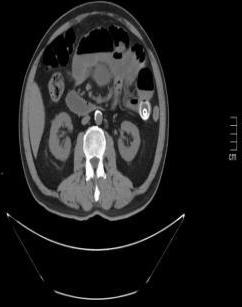

• 超声内镜引导下胃旁曲张静脉精准断流术治疗食管胃静脉曲张出血的疗效分析(附20例报告)

2025, 31(8):85-90. DOI: 10.12235/E20250036

摘要 (153) HTML (42) PDF 5.38 M (98) 评论 (0) 收藏

摘要:目的 探讨超声内镜引导下胃旁曲张静脉精准断流术治疗食管胃静脉曲张出血的疗效。方法 回顾性分析2024年1月1日-2024年12月31日于该院接受超声内镜引导下胃旁曲张静脉精准断流术治疗的20例肝硬化食管胃静脉曲张出血患者的临床资料,并评估治疗效果。结果 20例患者均顺利完成超声内镜引导下胃旁曲张静脉精准断流术;注射组织胶联合置入弹簧圈(16例)和单独注射组织胶(4例)均成功阻断胃旁来源的曲张静脉;所有患者均未发生穿孔、食管贲门狭窄、大出血、败血症和异位栓塞。1例单独注射组织胶的患者,术后胃旁曲张静脉少许渗血,经降低门静脉压力治疗3 d后好转,另1例单独注射组织胶患者,术后出现低热,抗感染3 d后体温恢复正常。结论 超声内镜引导下胃旁曲张静脉精准断流术治疗食管胃静脉曲张出血的临床疗效好,异位栓塞、大出血、感染和穿孔等并发症少,但仍需要密切随访,观察胃旁曲张静脉的排胶问题。